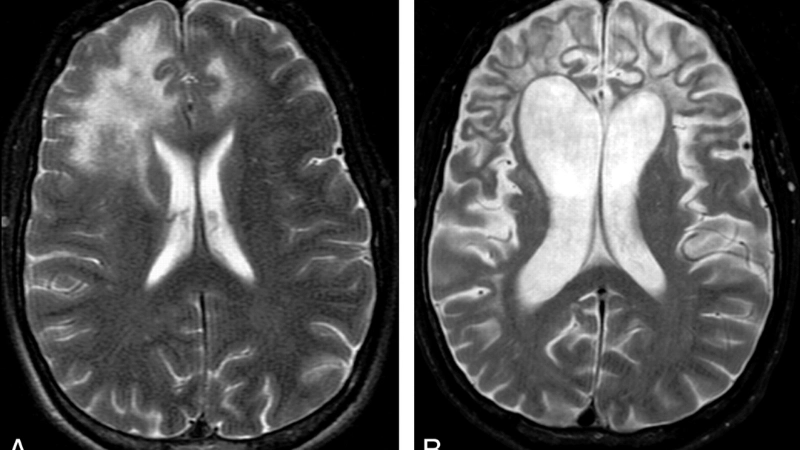

Progressive multifocal leukoencephalopathy cases show severe brain lesions